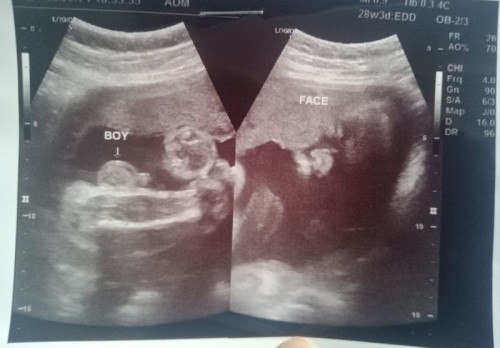

Ultrasound (Gender)

Hello Mommies, Nagpa ultrasound ako today (3/11/21).. Naka breech position si baby then naka de kwatro pa, kaya ayun 70% chance na baby boy ang tingin ni OB sa gender po.. Need pa ulit namin magpa ultrasound after 2 weeks to confirm 100% kung baby boy talaga.. Sino po sainyo naka experience ng ganito? Malaki kaya chance sa 2nd ultasound ko na ma confirm na baby BOY talaga siya? Base po sa mga naka experience ng ganito sana... 26 weeks na po pala ako.. Thank you *UPDATE: nagpa ultrasound po ulit kami, ayun kitang kita na po yung gender nya, naka cephalic position nadn ang baby BOY namin. Answered prayer 🙏😇😍 Thank you sa mga comments po #1stimemom #firstbaby #pregnancy